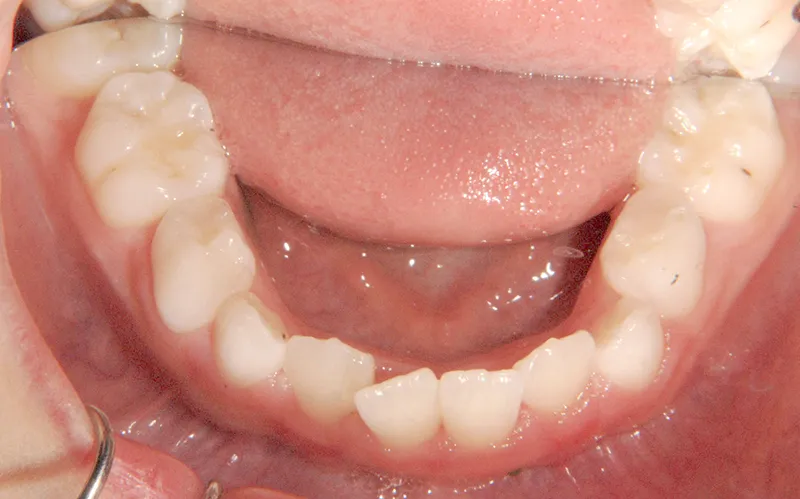

• 治療終了後

治療終了後

下の歯は永久歯の生えるスペースがないので、オリジナル矯正装置で受け口を治して、永久歯の生えるスペースを作りました。

治療回数19回、2年5ヶ月の治療期間で矯正治療を終了しました。

主訴が改善され、ご満足頂きました。